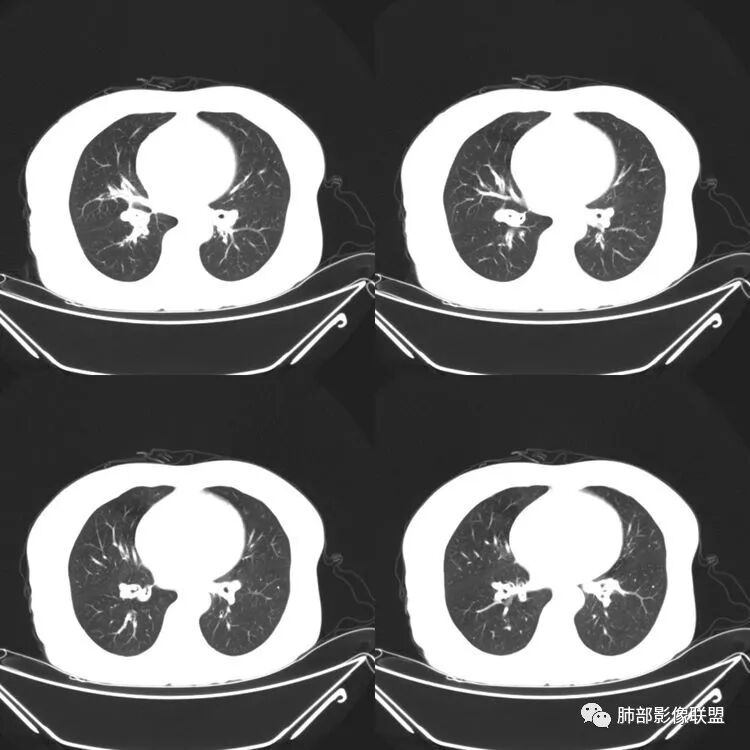

患者,女,64岁,反复咳嗽、咳痰、胸闷10年,加重2周患者10余年来每当受凉感冒出现咳嗽、咳痰、胸闷,有时痰中带血,输液治疗(具体不详)可好转。既往有声带肥厚手术病史。CT示气管、主支气管及分支支气管管壁弥漫性增厚累及膜部,局部伴钙化,管腔狭窄,考虑淀粉样变性

患者,女,64岁,反复咳嗽、咳痰、胸闷10年,加重2周。气管支气管及两肺下叶 支气管弥漫性的环状增厚,管腔扩张,管腔感觉比较松弛。第一感觉,气管支气管淀粉样变。鉴别诊断,1、支气管内膜结核,肺内散在一些支气管的播散病灶,粟粒结节为主,形态比较单一。2、复发性的多软骨炎,就得了解一下其他部位,有没有多个部位的软骨炎。这个病人右侧胸廓缩小,升主动脉明显的扩张,其横径明显的超过了降主动脉。

南边:肺部有肺气肿支气管腔狭窄淀粉样变性?复发性多软骨炎?血管炎?慢支?结核?曲霉菌?南边:一般还是淀粉样变性与复发性多软骨炎鉴别其次就是支气管骨化症,但是骨化下朝上,且壁结节状钙化明显,本例不太支持。至于结核、曲霉菌?1.结核,一般不会这么广泛,支气管壁狭窄后扩张2.曲霉菌可以这么广泛,但是支气管壁管腔扩张,而且附近脂肪间隙有炎性反应,不太支持;3.血管炎,一般合并肺内有病灶,但是声带受累,放待排;4.软骨炎一般全身受累,例如耳廓等;而且膜部不受累,不太支持;倾向于淀粉样变性;淀粉分很多型,气管支气管是最常见的。尘缘:影像上生理性钙化与支气管骨化无法区别,镜检也不好鉴别,需要依赖活检,看粘膜中是否合并炎性改变(淋巴细胞,组织细胞等炎性细胞侵润)来鉴别Coke with ice:经常看到的这种是老年性肺改变,又称年龄相关肺改变。气管和支气管弥漫性软骨钙化,常见老年女性。尘缘:支气管骨化症很罕见的,所以绝大多数还是生理性钙化。对于老年人,无临床症状的钙化,还是基本上都是生理性钙化,无临床意义。大雄:如果管壁钙化伴明显增厚 影像还是提示一下建议支气管镜稳妥些

病理结果:肺淀粉样变

气管支气管淀粉样变性

三、影像表现

1.气管支气管型

①气管支气管壁增厚,形成粘膜下斑块与结节

②管腔广泛狭窄、闭塞

③管壁钙化

④膜部受累(具有重要鉴别意义)

---鉴别诊断

①骨化性气管支气管病

主要是由于气管支气管壁软骨化生及异位软骨瘤形成,气道膜部没有软骨,所以不累及膜部,气管壁结节样增厚伴钙化。

②复发性多软骨炎

多系统受累,常累及鼻、耳廓等其他部位的软骨,气道膜部没有软骨,所以膜部也不受累,气管及支气管壁平滑增厚,管壁钙化,管腔弥漫性缩窄,外壁模糊。